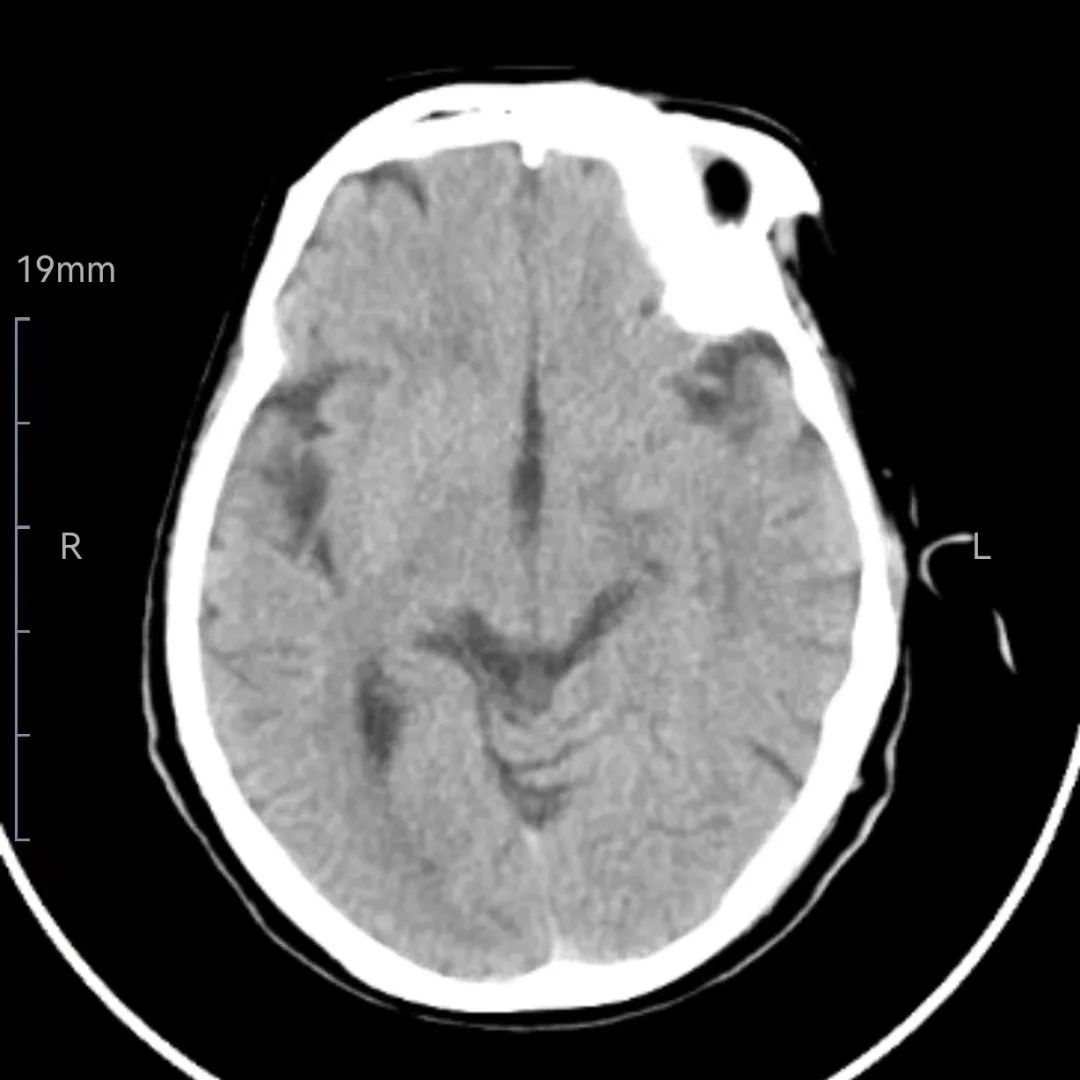

2月8日上午11:05,该院神经内科病区突然传来一阵急促的电话铃声,急诊一名患者言语不能伴右侧侧肢体无力2小时余,已开通卒中绿色通道。简单快速询问后,郝宪军主任和康敏毅医师以及护士携带溶栓箱快速到达急诊科。经评估,患者(9:20)出现言语不能、右侧肢体无力、症状持续,急诊查头颅CT未见出血,NIHSS评分16分(意识2,凝视1、面瘫1、右上肢运动4、右下肢运动4、感觉1、语言3)。

溶栓前头颅CT 抓住抢救“黄金时间”